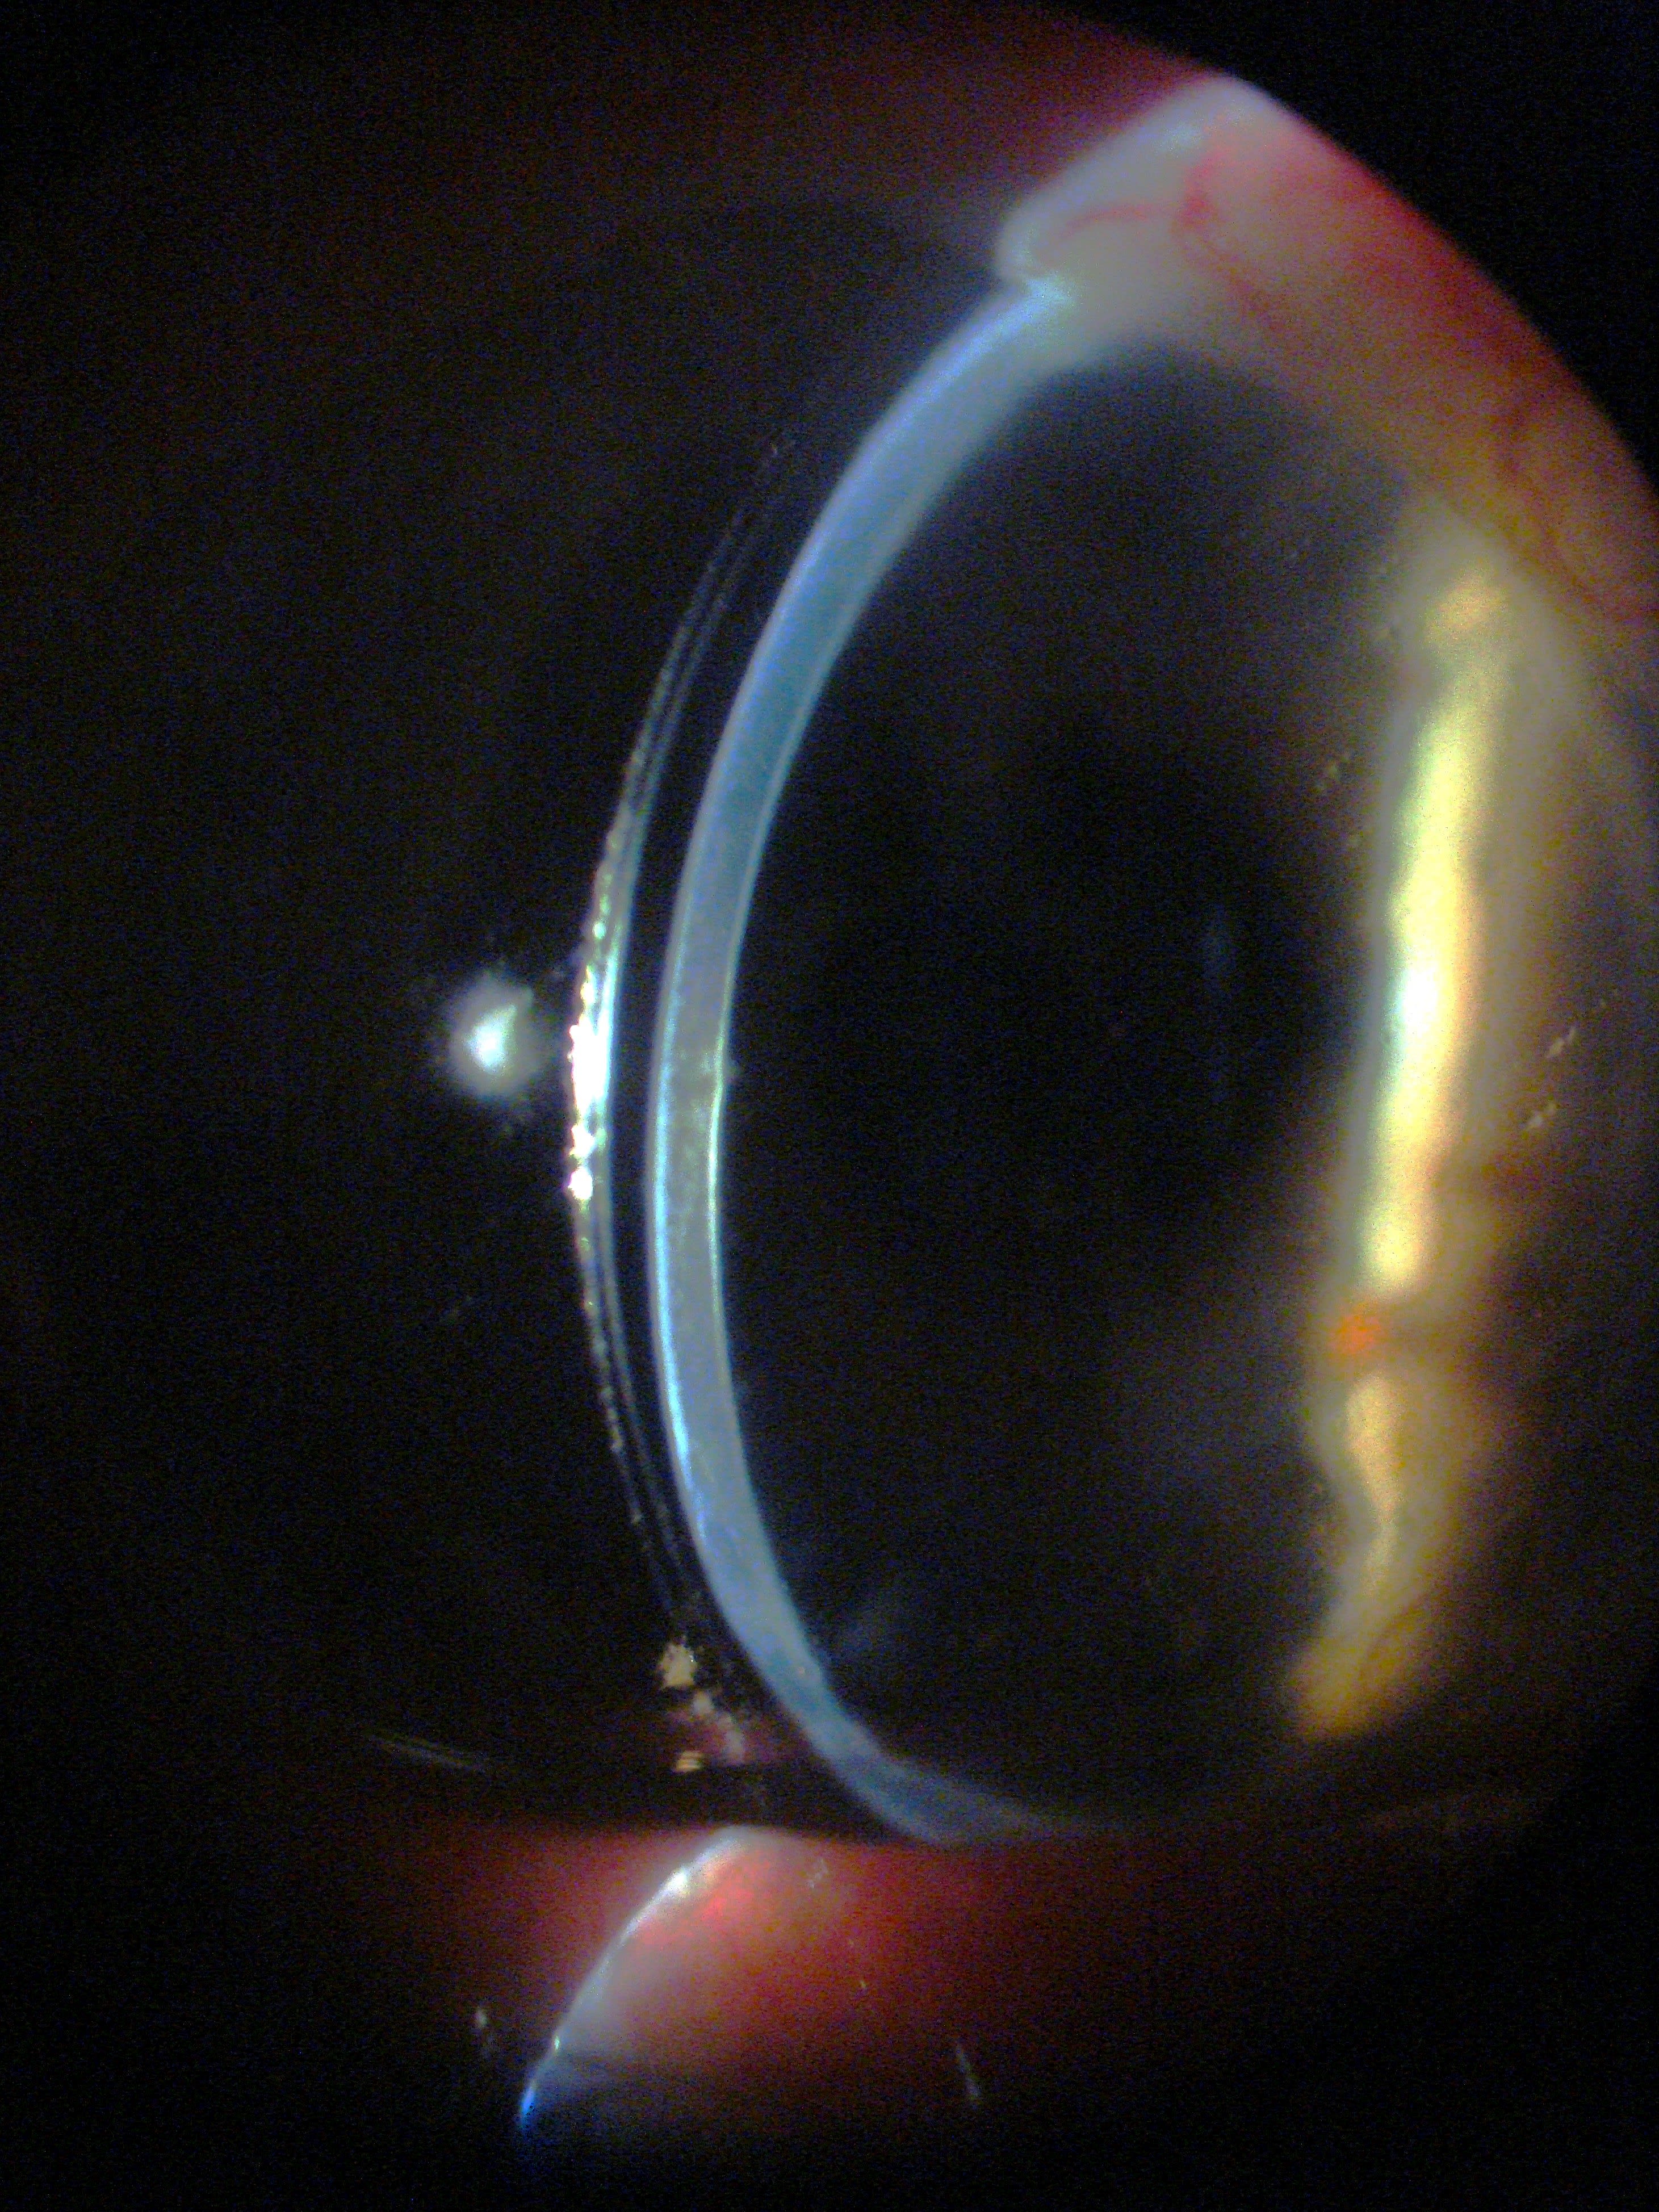

The patient alternated between the corneal GP and scleral lens to minimize symptoms. Slit lamp evaluation showed excessive clearance centrally and over the limbus (Figure 1).

The post-graft elevation required vaulting, with the central cornea flatter than the periphery.

In this patient, prolapse was likely exacerbated by excessive superior vault. The large amount of superior vault was due to high overall vault and a landing zone transition not optimized for the shape of the corneal graft to sclera (Figure 2).